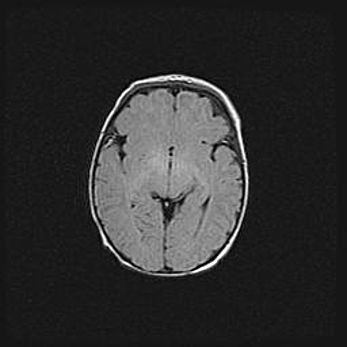

Церебральная ишемия II.

Возраст: 5 дней

Вес: 3400 г

Пол: женский

Окружность головы: 35 см

Срок гестации: 39 недель

Церебральная ишемия – это заболевание, характеризующееся недостаточностью (гипоксией) либо полным прекращением (аноксией) снабжения мозга кислородом по причине закупорки одного или нескольких сосудов. Это приводит к  что метаболическим расстройствам различной степени тяжести в тканях головного мозга, развитию коагуляционных некрозов и гибели нейронов.